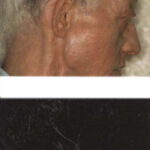

ALEZZANDRINI SYNDROME

The constellation of clinical findings in Alezzandrini syndrome includes facial vitiligo, poliosis, deafness, and unilateral tapetoretinal degeneration. The etiology remains poorly understood, but as in vitiligo and VKH syndrome, autoimmune processes are thought to be involved. Only a few cases have been reported since the first description of a patient with vitiligo, poliosis, and unilateral retinitis in 1959.23